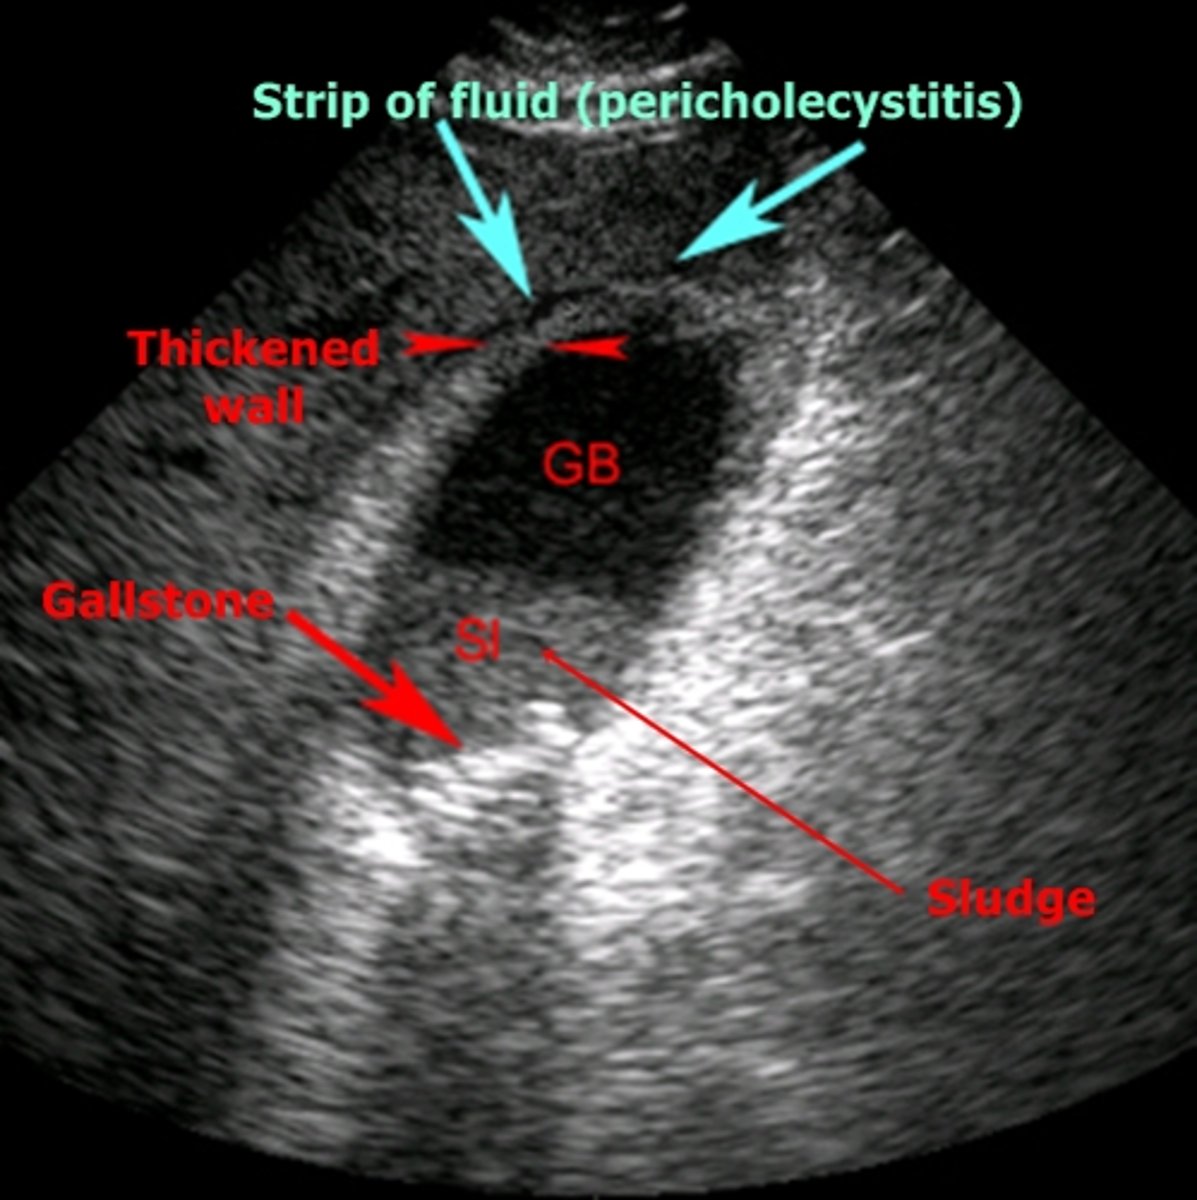

cholecystitis

inflammation of the gallbladder, usually caused by gallstone blocking outflow of bile through bile duct

-cystic duct most commonly obstructed

biliary sludge

aggregation that may contain cholesterol crystals, bilirubin, glycoprotein, often associated with biliary stasis

echogenic in gallbladder lumen, no acoustical shadowing

cholecystitis imaging

US- used most commonly, not best option

HIDA scan- useful for obstructed biliary duct, 96% sensitivity 90% specificity

MRI- 88% sensitivity 89% specificity

CT- may show perf or gangrene